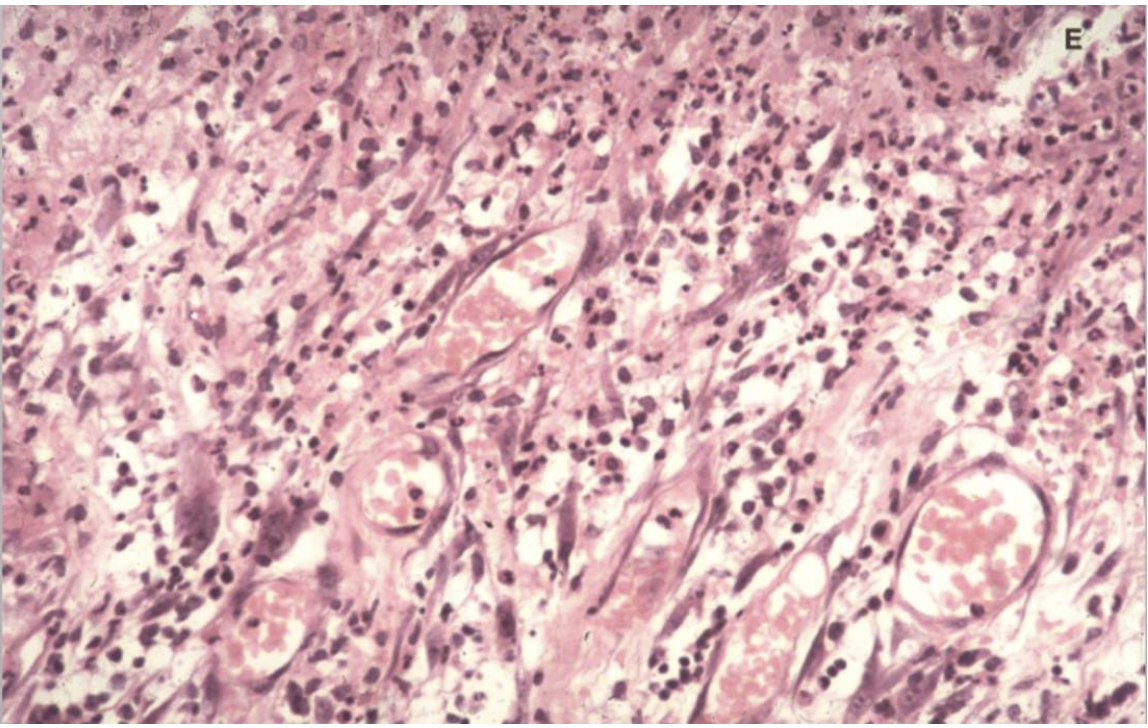

What can you see in this image?

Blood vessels and lymphocytes